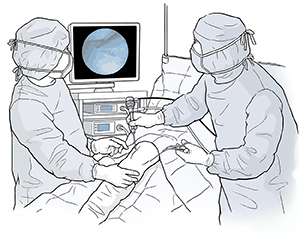

An arthroscope is a small tube that is inserted into the body. It contains a system of lenses, a small video camera, and a light for viewing. The camera is connected to a monitoring system that lets a surgeon view the surgery while it's being done. The arthroscope is often used with other tools that are put through another cut or incision. These tools are used for grasping, cutting, and probing.

Each procedure will vary. But generally, arthroscopic surgery follows this process:

A small incision is made in your skin.

The arthroscope is inserted through the incision.

Other incisions may be made to introduce other small grasping, probing, or cutting tools.

Light is sent via fiber optics at the end of the arthroscope.

Information about the inside of the joint is sent to a screen.